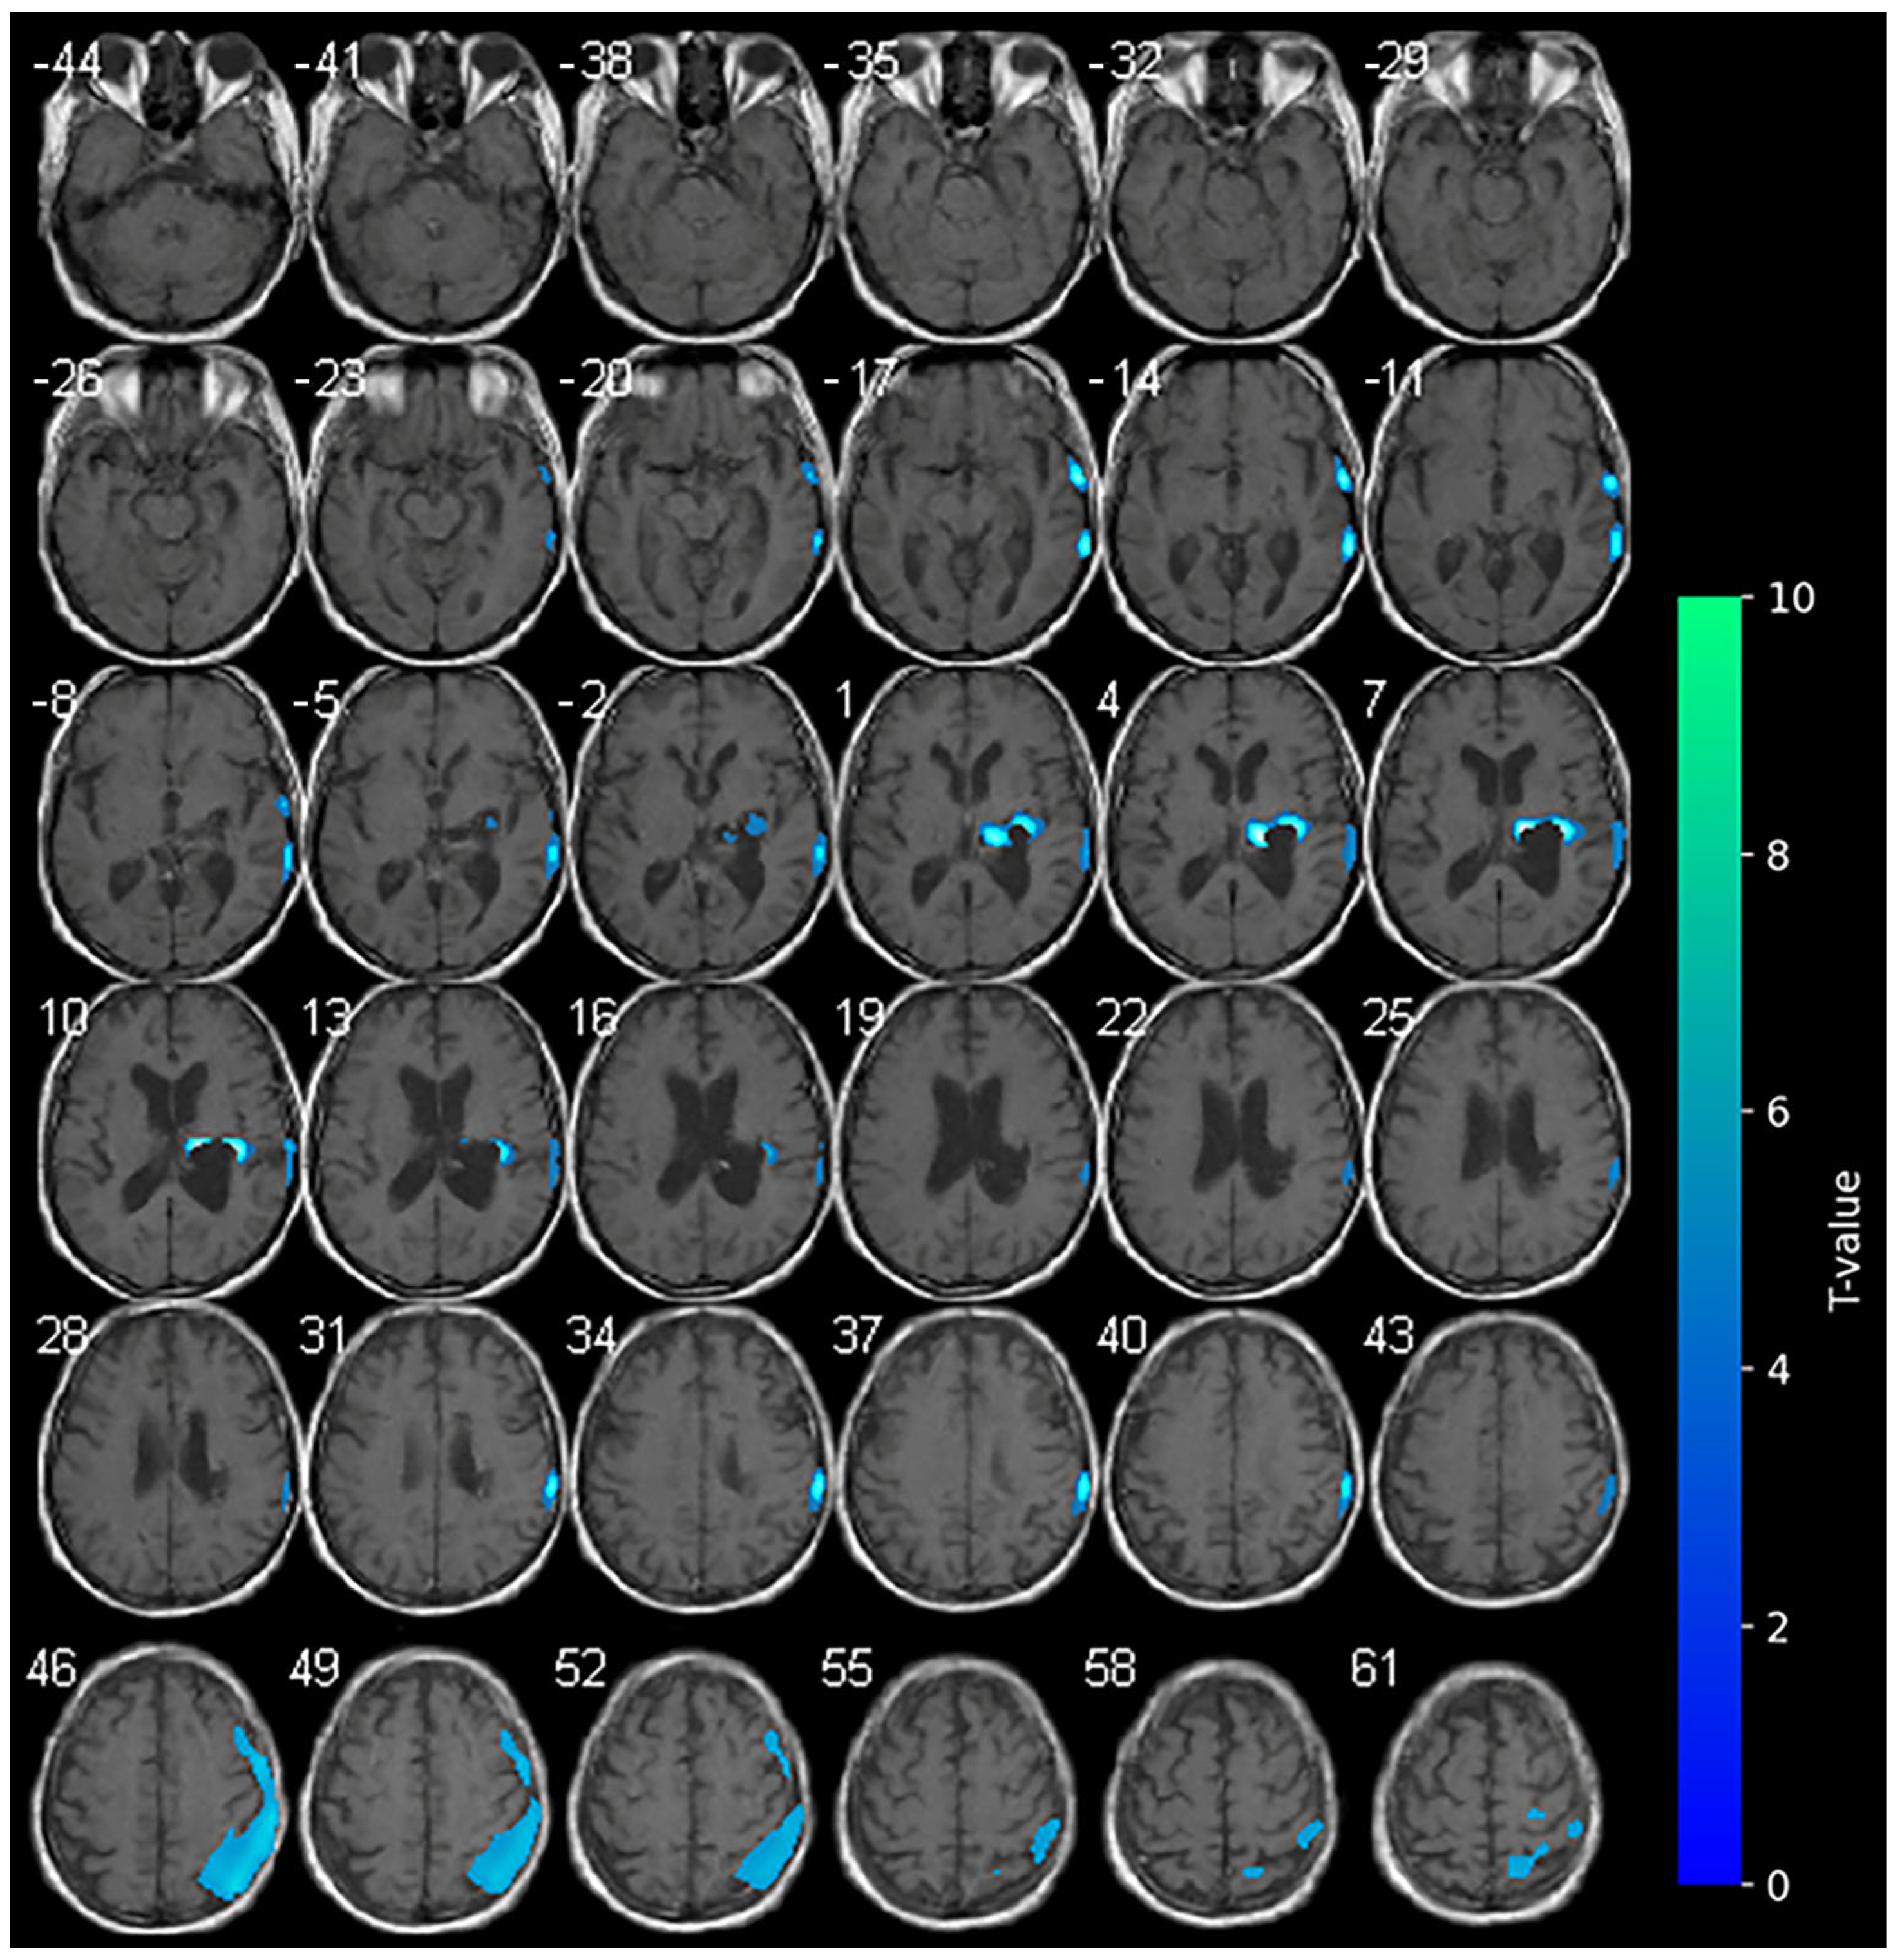

At the baseline, cerebral 18F-FDG-PET documented marked hypometabolism in the right nucleo-capsular hemorrhagic lesion and reduced uptake of the tracer on the right side at the superior and middle temporal gyrus, supramarginal gyrus, cingulate gyrus, and precentral gyrus (Figure 1). At the baseline (T0–week 2), the clinical picture of the enrolled subject was characterized by marked neurological impairments (as indicated by an NIHSS score of 19 and an mRS score of 5), suggesting severe disability in daily activities. The patient exhibited a complete loss of motor function, as evidenced by an MI score of 0 in both upper and lower limbs. Furthermore, the subject displayed impaired consciousness, with the LCF scored at 5. While the subject demonstrated capacity to respond to simple commands, their performance was non-purposeful and fragmented when complex commands were issued. Gross attention to the environment was evident; however, the subject demonstrated an inability to concentrate on specific tasks. Verbalization was often confabulatory, and the memory was notably compromised, with limited capacity for the retention of new information. The subject’s behavior was deemed to be appropriate.

Figure 1. Axial slices showing the results of the SPM analysis (t-maps) at the baseline. The blue areas indicate the locations where the voxel values of the patient were significantly hypometabolic from the normal control group (p > 0.001). The brightness of the color represents the t-value.